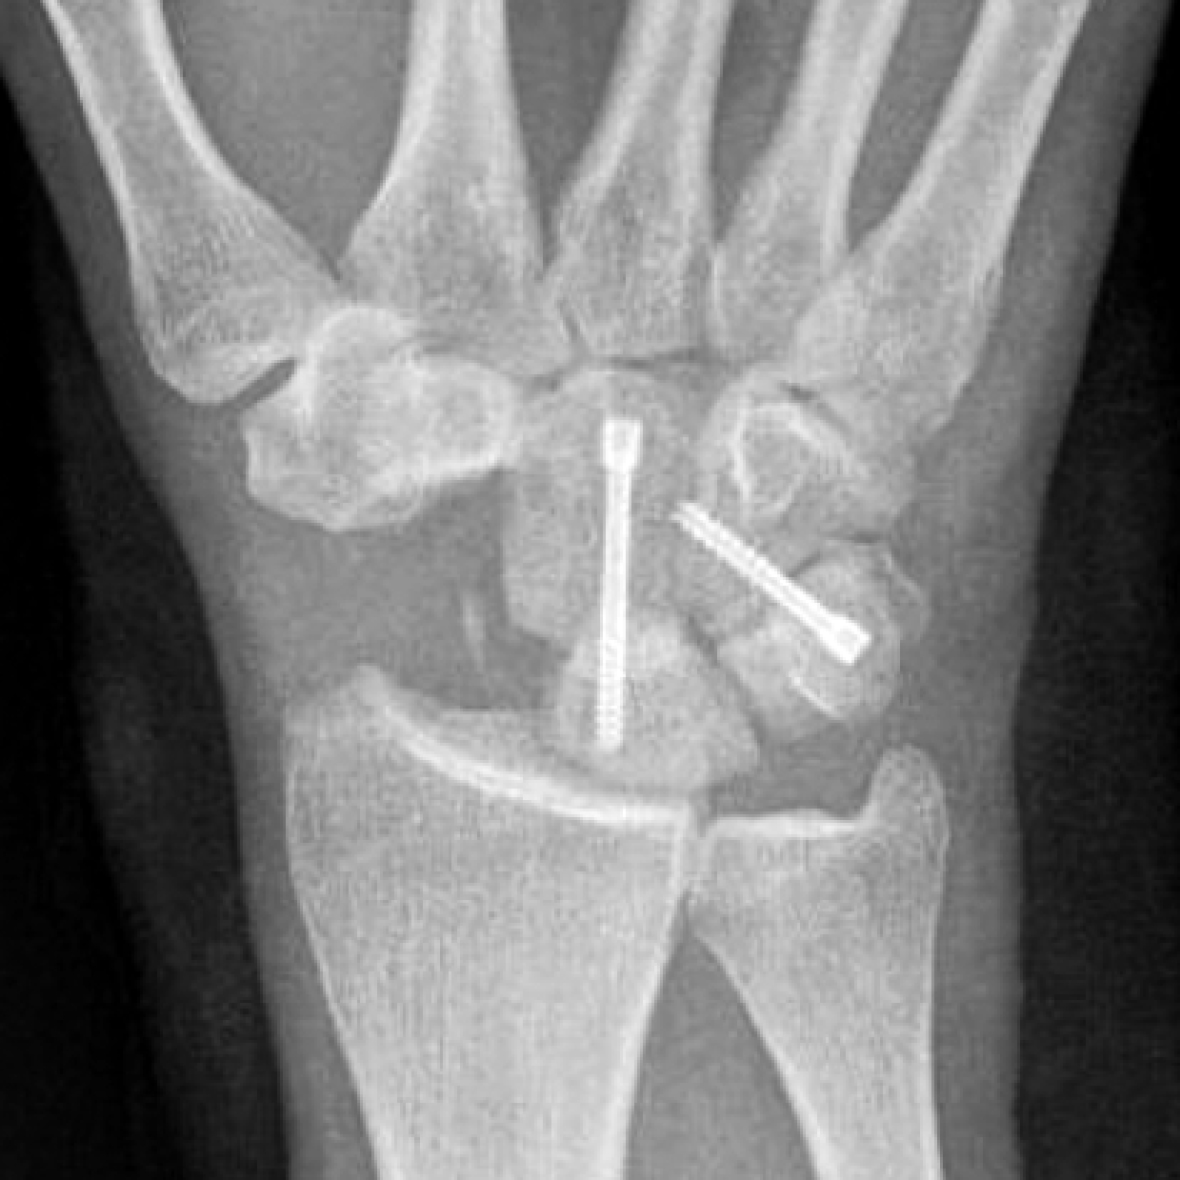

Резекция проксимального ряда костей запястья (proximal row carpectomy — PRC) может быть рекомендована при I, II и III стадиях SLAC с минимальным поражением хряща головчатой кости [45] (рис. 2). Следует иметь в виду, что вновь сформированный сустав между головчатой и лучевой костями не конгруэнтен, с течением времени первоначально хорошие результаты операции могут ухудшаться, поэтому PRC не рекомендуется выполнять пациентам моложе 35 лет [46].

Рис. 2. Фрагмент рентгенограммы кисти пациента c II стадией SLAC в первые сутки после резекции проксимального ряда костей запястья

Figure 2. X-ray fragment of a patient with SLAC stage II wrist on the 1st day after proximal row carpectomy